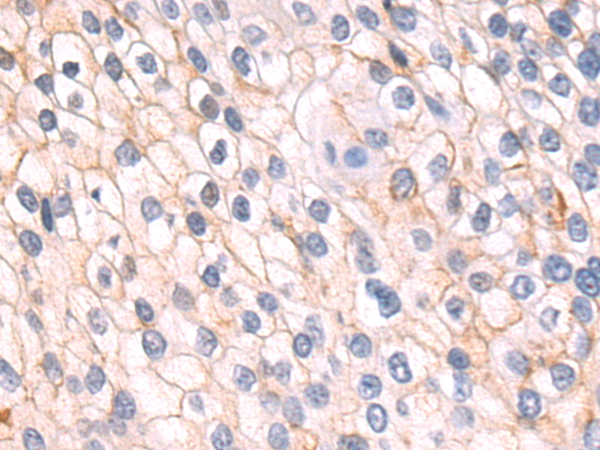

分类: 科研抗体货号: P02597别名: dJ94G16.1应用: IHC反应种属: Human

分类: 科研抗体货号: P02715别名: ACAD2应用: IHC反应种属: Human, Mouse, Rat

分类: 科研抗体货号: P02665别名: GBL; LST8; POP3; WAT1; GbetaL应用: IHC反应种属: Human, Mouse, Rat

分类: 科研抗体货号: P02588别名: GRP1; ARNO3; PSCD3; cytohesin-3应用: IHC反应种属: Human, Mouse, Rat